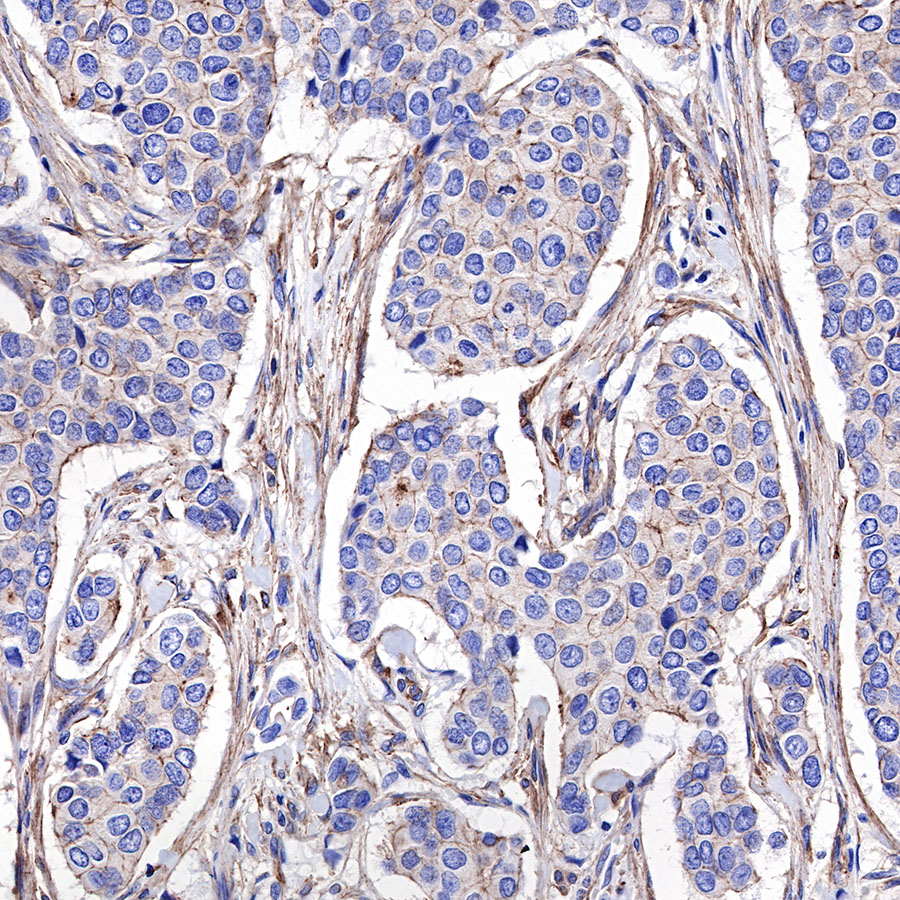

IHC shows positive staining in paraffin-embedded human colon. Anti-α-Actinin-1 antibody was used at 1/2000 dilution, followed by a HRP Polymer for Mouse & Rabbit IgG (ready to use). Counterstained with hematoxylin. Heat mediated antigen retrieval with Tris/EDTA buffer pH9.0 was performed before commencing with IHC staining protocol.

IHC shows positive staining in paraffin-embedded human colon cancer. Anti-α-Actinin-1 antibody was used at 1/2000 dilution, followed by a HRP Polymer for Mouse & Rabbit IgG (ready to use). Counterstained with hematoxylin. Heat mediated antigen retrieval with Tris/EDTA buffer pH9.0 was performed before commencing with IHC staining protocol.